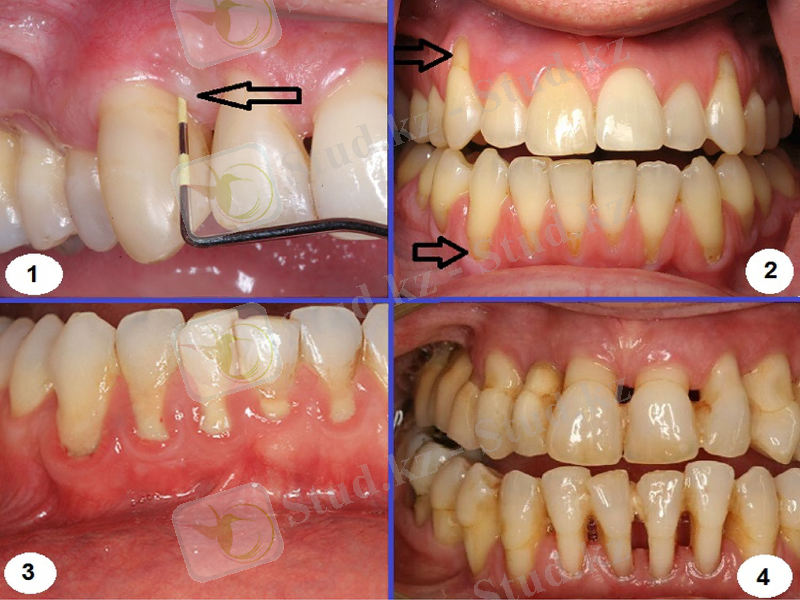

Пародонтоздың орташа дәрежесі

Шағымы: тістің клиникалық сауытының ұзарғанының нәтижесінде косметикалық ақауға

Сырттай қарап тексеру: қызылиек жиегі бозарған, тіс түбірі беткейіне тығыз орналасқан, түбір ұзындығының1/3 бөлігі деңгейінде біркелкі жалаңаштануы, тістер қозғалғыштығы анықталмайды, жарақаттық окклюзия, диастема және тремалардың пайда болуы, тіс қақтары болмайды немесе шамалы анықталады.

Зондылау: тіс-қызылиек байланысы бұзылмаған, қанағыштық жоқ.

Рентгенография: кортикальды пластинка сақталған, тісаралық қылқан биіктігінің 1/2 бөлігі жайылмалы біркелкі төмендеуі. Остеосклероз ошақтарымен остеопороз ошақтарының альвеола өсіндісінің сүйек тінінде кезектесуі.

Пародонтоздың ауыр дәрежесі

Шағымы: тістің клиникалық сауытының ұзарғанының нәтижесінде косметикалық ақауға, ½ бөлігінен аса ұзындықта түбірлердің жалаңаштануы, көптүбірлі тістер бифуркациясының, тіс аралық кеңістіктердің жалаңаштануы, тісжегі емес зақымданулар байланысты байланысты болуы мүмкін(гиперестезия, патологиялық қажалу, сына тәрізді ақау)

Сырттай қарап тексеру: қызылиек жиегі жұқарған, атрофияланған, болғылт түсті, тіс түбірі беткейіне тығыз орналасқан, бифуркациясының жалаңаштануы, ½ бөлігінен аса ұзындықта түбірлердің жалаңаштануы, диастема, трема, тістер қозғалғыштығы анықталмайды, тіс қақтары болмайды немесе шамалы анықталады.

Рентгенография: тісаралық қылқан биіктігінің 1/2 бөлігінен аса жайылмалы біркелкі төмендеуі, кортикальды пластинка сақталған, альвеола өсіндісінің сүйек тінінде остеосклероз ошақтарымен остеопороз ошақтарының кезектесуі.